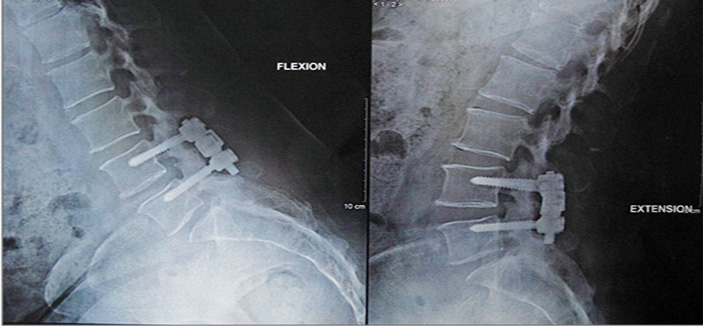

أوضح ذلك الدكتور دومنييك سماحه رئيس الفريق الطبي واستشاري أمراض العمود الفقري الحاصل على الزمالة الفرنسية ، وأضاف بأن التقنية الجديدة تعرف باسم « dynamic stabilization of the lumbar spine « والتي تفيد في تثبيت فقرات العمود الفقري بصورة أفضل من ذي قبل للحفاظ على نوعية الديسك الموجود أعلى الفقرات المتضررة. مفيداً بأن التثبيت الديناميكي الجديد فكرته تقوم على وجود عمودين بداخلهما جزء صغير للعمل على امتصاص الصدمات وتأمين التثبيت اللازم للفقرات المطلوب تثبيتها. وهذا النظام الجديد يؤمن حركة للمريض عشر درجات من الأمام وللخلف مقارنة بالتثبيت غير الديناميكي المستخدم سابقاً. وأشار د. سماحه إلى أنه تم إجراء هذه التقنيات بكثرة وقد لاقت نجاحاً كبيراً في دول أوروبا والولايات المتحدة الأمريكية ، وذلك لندرة حدوث المضاعفات وصغر حجم الجرح أثناء العملية لتطبيقه تقنيات الفتح الصغير والمعروفة باسم (Bilateral Mini invasive) مما يساعد في سرعة الشفاء والرجوع لممارسة الحياة الطبيعية والتوفير المادي لعدم الحاجة إلى إجراء العملية مرة .

وفي الختام قال الدكتور سماحه بأن لهذه التقنية الجديدة هدفين الأول هو توفير الحركة لبضع درجات في المستوى المثبت مع تجنب تدهور المستوى العلوي. مشيراً إلى أن الهدف الثاني هو السماح للجراح بفضل هذه التقنية أن يقوم بتثبيت الفقرات دون حدوث أية مخاطر على النخاع الشوكي والأعصاب وتجنب الآثار الجانبية على العضلات.علاوة على أن هذه التقنية تسمح بتقليص مدة التماثل للشفاء والعودة للحياة الطبيعية بشكل أسرع.